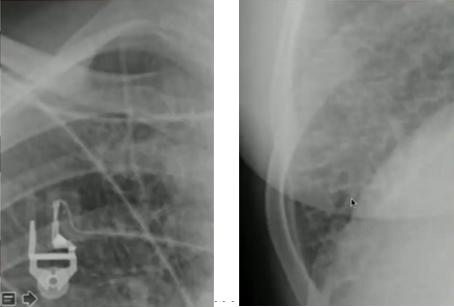

图14.“脊柱征”:位于心影后的下叶肺炎在正位片中不易看出,侧位片中可表现为椎体变白

正常侧位片(左)与下叶肺炎(右)

图15.沿肺门分布的线条状阴影,不累及胸膜边界

图16.正位片(左):肺不张(右上肺野肺裂上移);侧位片(右):过度充气(横隔变平)